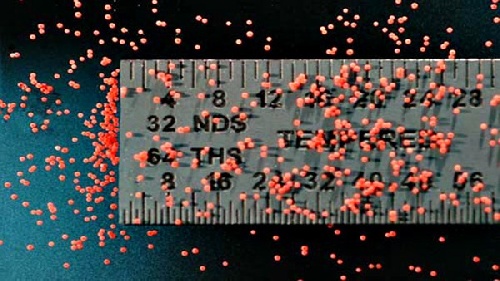

قیمت: 41٬000 تومان - دسته بندی فایل: پاورپوینتپاورپوینت استفاده از ریزکپسول سازی در مبارزه با کمبود آهن

پاورپوینت استفاده از ریزکپسول سازی در مبارزه با کمبود آهن